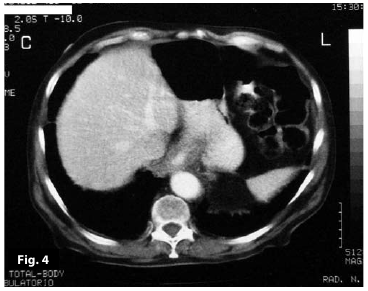

Figure4